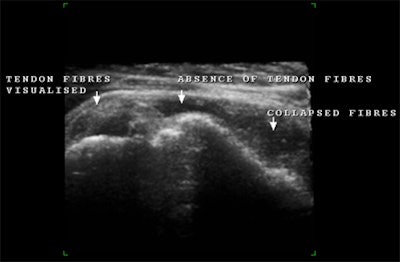

![]() |

| Multiplanar and 3D imaging of a completely ruptured biceps tendon. This is a study of an elderly patient who, after having lifted a heavy load, presented with weakness of the arm and swelling at the level of the middle of the humerus. One must follow the length of the biceps tendon from its origin to its insertion with the muscle. With acute traumatic rupture of the biceps tendon, the muscle contracts and collapses upon itself distally while the tendon retracts as in the above case. All planes demonstrate a fluid collection within the biceps sheath, the absence of any tendon fibers throughout the fluid collection, and the collapsed biceps muscle beneath. |